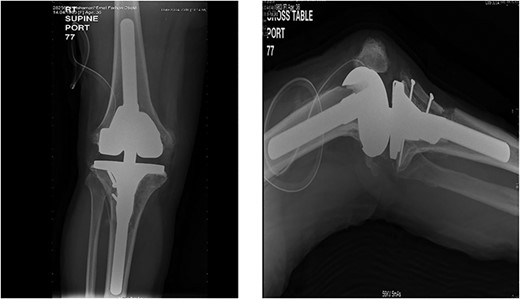

A 32-year-old female known case of rheumatoid arthritis affecting both knees presented to our clinic complaining of severe right knee stiffness post TKA 4-years-ago done in an outside facility (Figs. 1 and 2). She lives in a rural community and was on hydroxychloroquine, but her disease was active as she was not compliant to her medication. On physical examinations, the right knee was larger in size compared to the left knee without joint effusion. Range of motion was zero on flexion, −10° in extension. Standing knee X-ray showed HO around the prosthesis (Fig. 2). Computed tomography (CT) demonstrated extensive HO with implants fixed in place (Fig. 3). Revision surgery and replacement of the prostheses was considered to restore function.

Preoperative standing X-ray showing heterotopic ossification around the prosthesis with preserved knee joint. (A) Heterotopic bone extending proximally on the anterior surface of the femur. (B) Posterior heterotopic bone fusing the knee joint. Careful removal with osteotomes and bone curettes was necessary to remove the old implants.